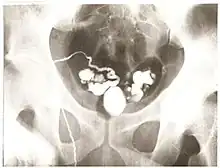

Vasography is an X-ray study of the vas deferens to see if there is blockage, oftentimes in the context of male infertility.[1] An incision is made in the scrotum, contrast is injected in the vas deferens, and X-rays are taken from different angles.[1] Thus, it is an invasive procedure and carries risk of iatrogenic scarring and obstruction of the vas.[2] Vasography has traditionally been considered the gold standard imaging modality for evaluating the seminal tract patency.[3]

Vasography was first described by Belfield in 1913, where a vasotomy was initially done and the vas deferens was subsequently intubated.[4][5] After almost 40 years of being overlooked, Boreau revived the procedure in the 1950s.[4] Then, vasography was somewhat overused for various fertility disorders and other diseases such as tuberculosis, prostate cancer, hemospermia, and compressive fibrolipomatosis, without considering the possible risks and complications from the procedure.[4] Today, vasography is used to determine the location of obstruction in azoospermic patients who have demonstrated spermatogenesis by testis biopsy.[6]

Vasography is absolutely indicated if 1) azoospermia (low sperm) is present, 2) testis biopsy shows complete spermatogenesis and many mature spermatids, and 3) there is at least one palpable vas.[7]

Vasography may be indicated if there is severe oligospermia (few sperm) with a normal testis biopsy, high levels of sperm-bound antibodies, or low semen volume and poor sperm motility.[7]